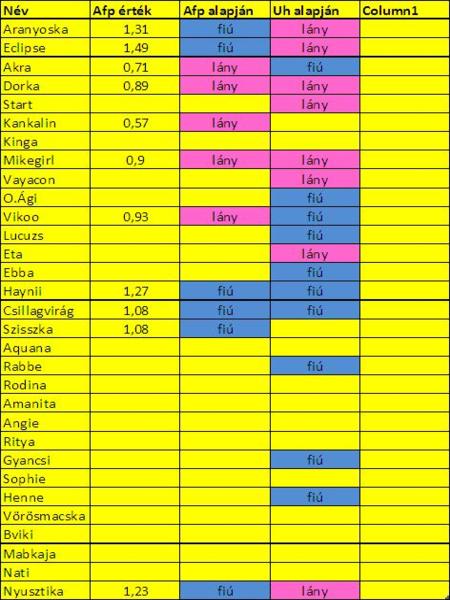

AFP statisztika jó ötlet! kíváncsi leszek a végeredményre!